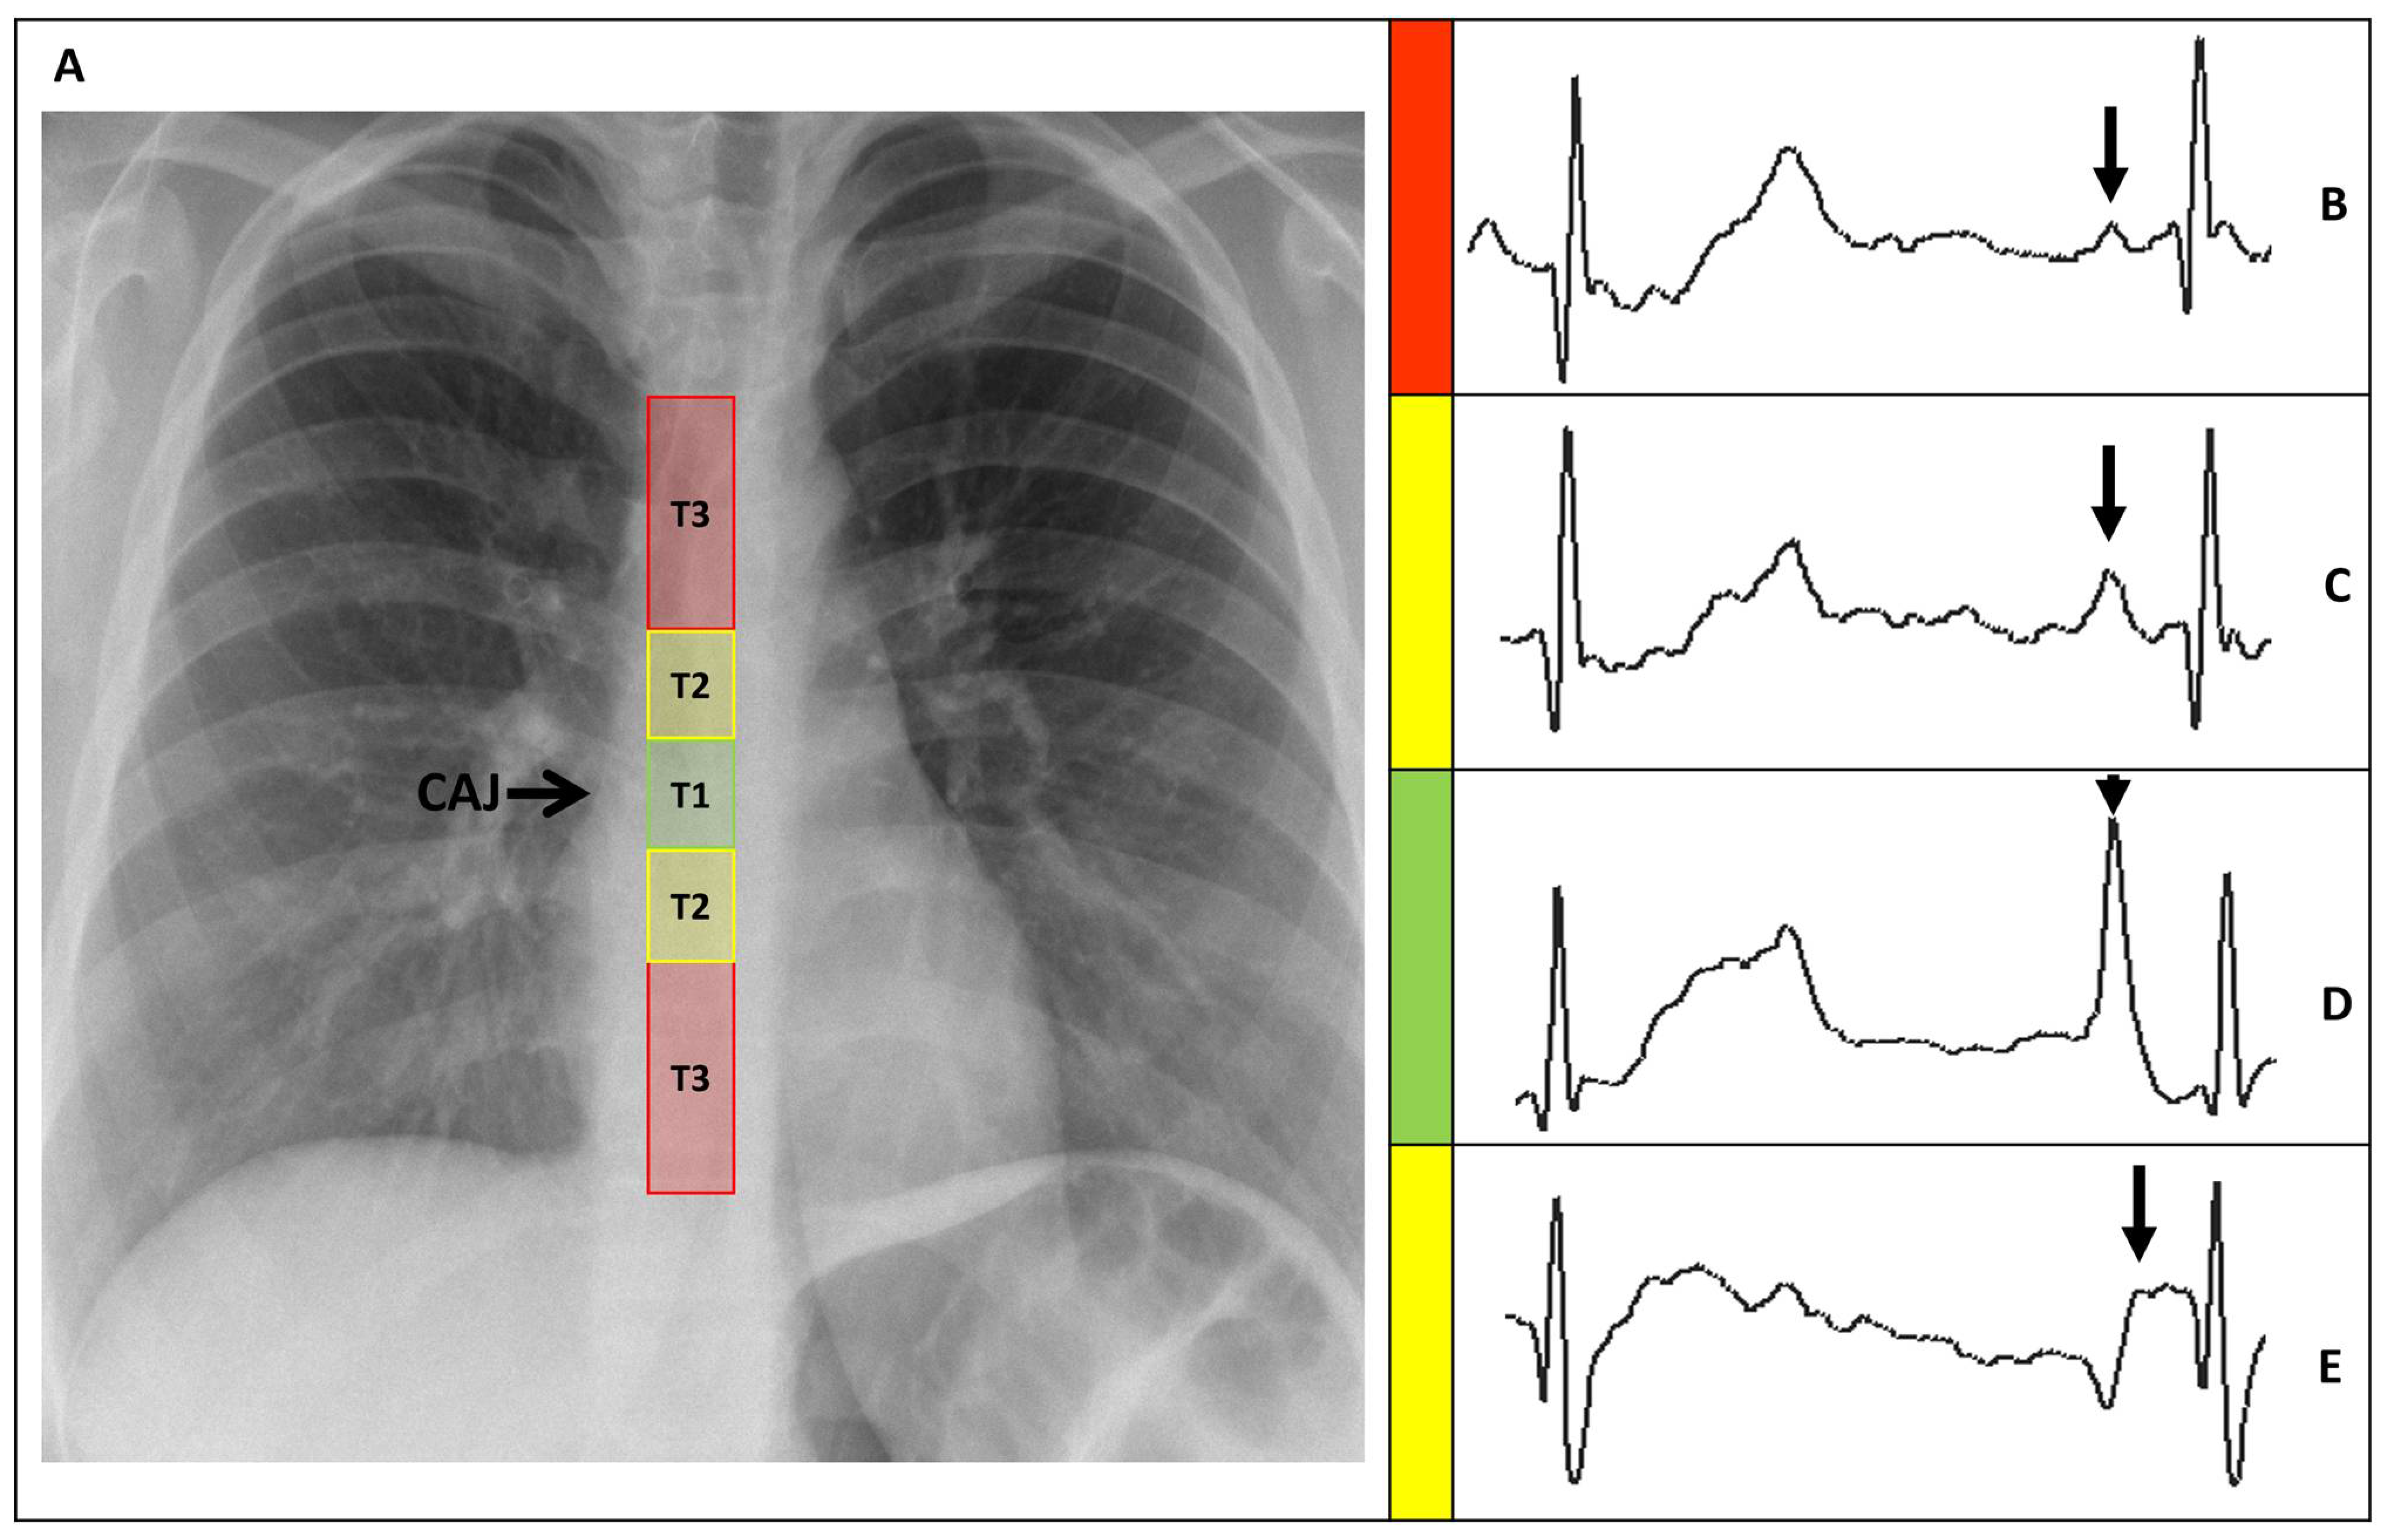

Figure 7. External and intravascular ECG trace of the Wire-based technique (WT) and Saline conduction technique (ST). (A) WT trace featuring maximal P-wave at the level of CAJ (open arrow). (B) ST trace featuring maximal P-wave at the level of CAJ (open arrow). (C) WT trace featuring initial negative deflection just beyond the level of CAJ (closed arrow). (D) ST trace featuring initial negative deflection just beyond the level of CAJ (closed arrow). (E) ST trace displaying important drifts (dashed arrow). CAJ, cavoatrial junction.